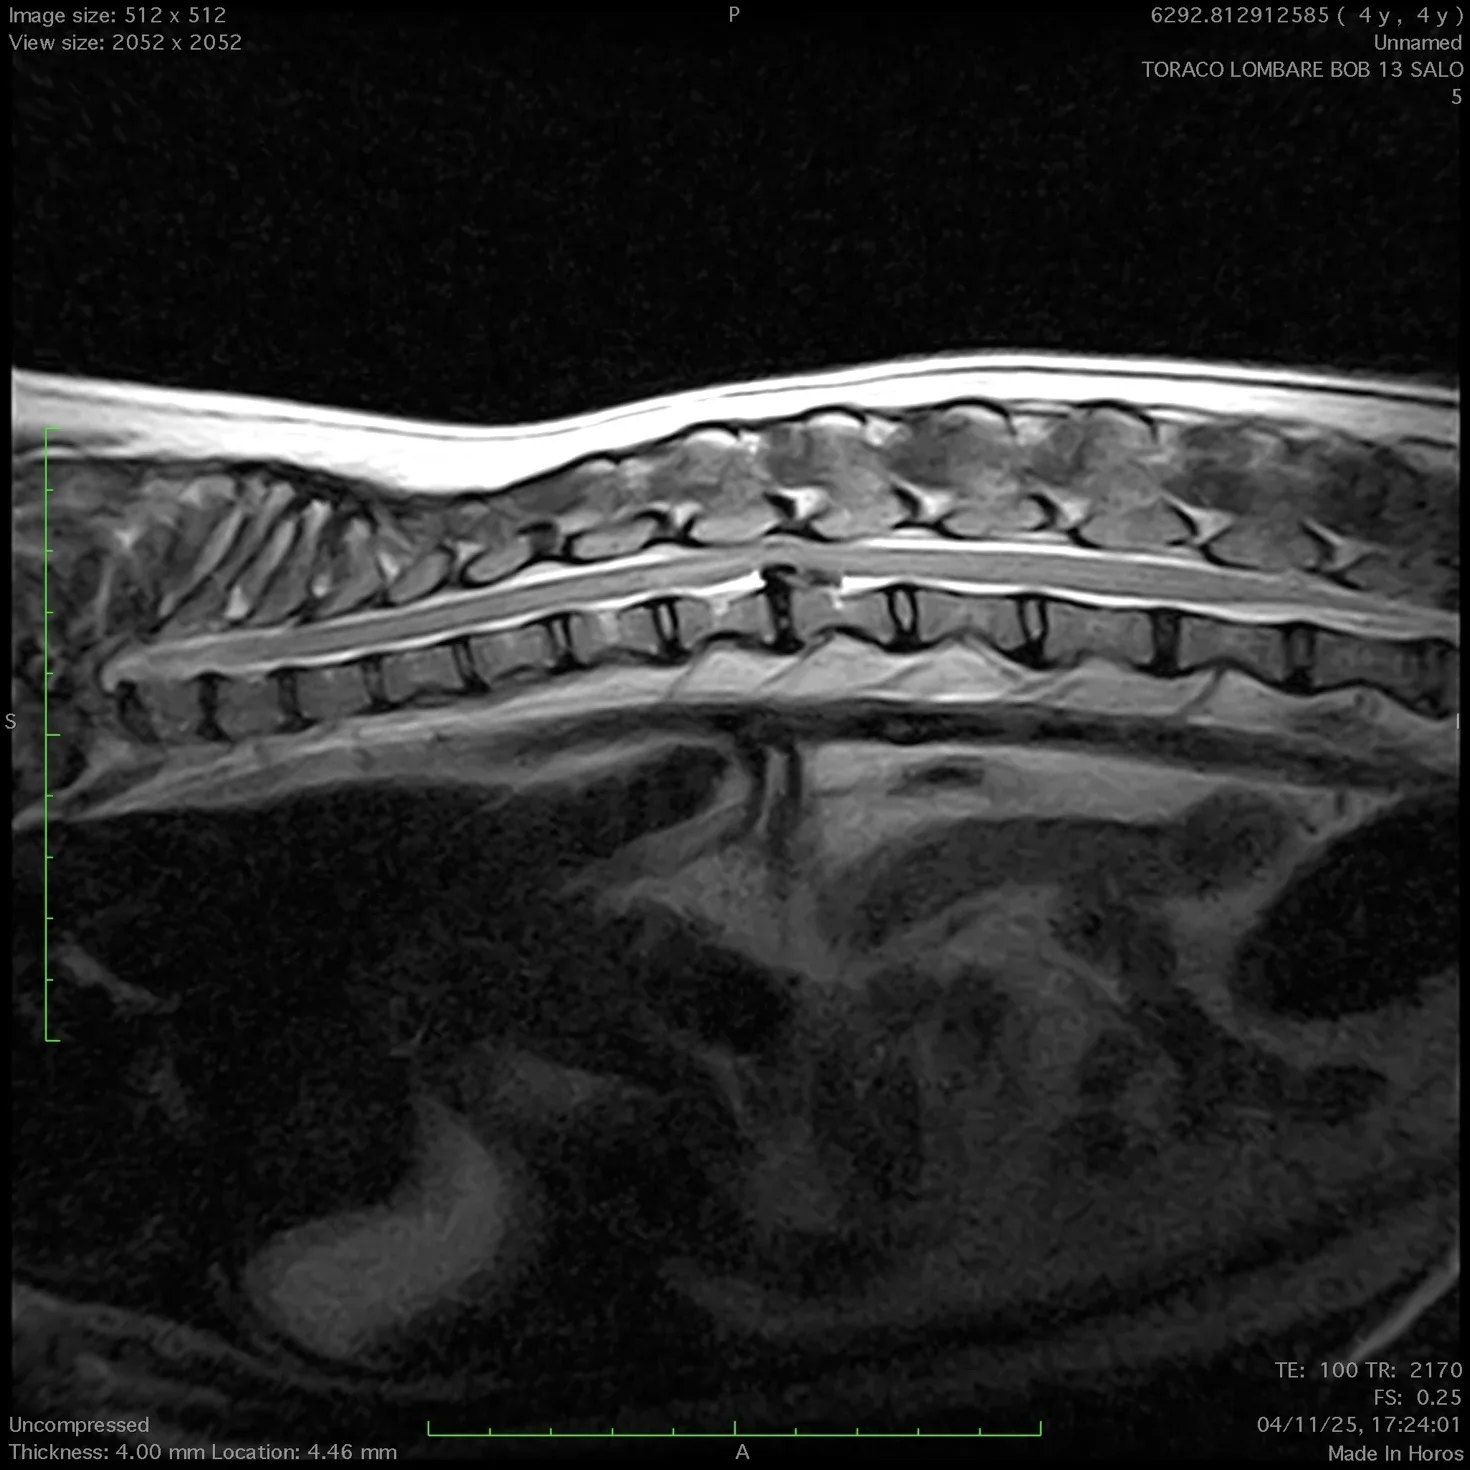

Successivamente alla visita, dopo aver effettuato esami e approfondimenti con ecografie e quanto necessario in genere, per effettuare la diagnosi ,si procede all’esecuzione di  un esame di risonanza magnetica nella sede di interesse ( encefalo o colonna vertebrale).

Con questa procedura chirurgica si eseguono interventi alla colonna vertebrale per la rimozione di ernie del disco che portano alla paralisi degli arti.

In caso di ernie del disco la procedura è molto urgente e se eseguita nei tempi previsti permette la guarigione del paziente nel 98% dei casi.

E’ possibile altresi rimuovere neoplasie esterne al midollo  ( lesioni intradurali o extradurali) ed in taluni casi selezionati  si possono rimuovere neoplasie encefaliche (meningiomi) .